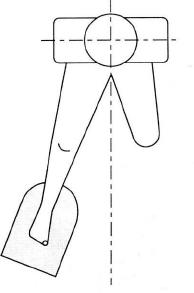

不正確超聲耦合劑用量不充分且位置

跟骨骨密度檢測不正確坐姿示意圖